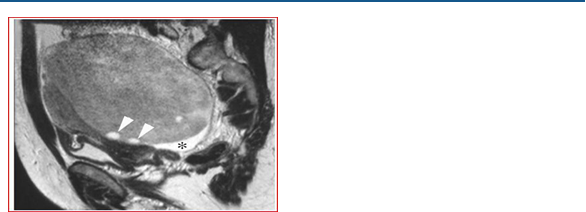

MRI shows a mass-free uterus, with no evidence of normal ovaries. The masses are approximately 13 cm in diameter and have low signal intensity on T1-weighted images and increased avidity after gadolin administration. On T2-weighted images the mass is hyperintense and the peripheral lesions probably correspond to ovarian follicles (Figures 4-6).

Figure 6: Sagittal T2-weighted MRI image of the pelvis, shows that the ovarian mass posterior to the uterus has an heterogeneous, intermediate-high signal intensity, the follicles in the periphery (arrow points), have a high signal intensity. The asterisk highlights the free liquid in the Douglas cord.

Figure 11: Sagittal T2-weighted MRI image shows that the tumor has intermediate signal intensity (open arrows) and there are hyperintense septal structures within the tumor (arrowheads). In the contralateral ovary there are three disconnected nodules (black arrows).

Figure 12: Sagittal T1-weighted MRI image, septa show increased signal intensity after administration of gadopentetate dimeglumine (arrowheads).

Figure 13: Axial T1-weighted MRI images with gadopentetate dimeglumine administration show many small, uniformly sized, smooth-walled cysts at the periphery of the mass (arrowheads).